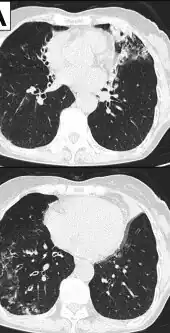

Image indicate bronchodilation, centrilobular granular shadow, and consolidation -

Chest radiograph -